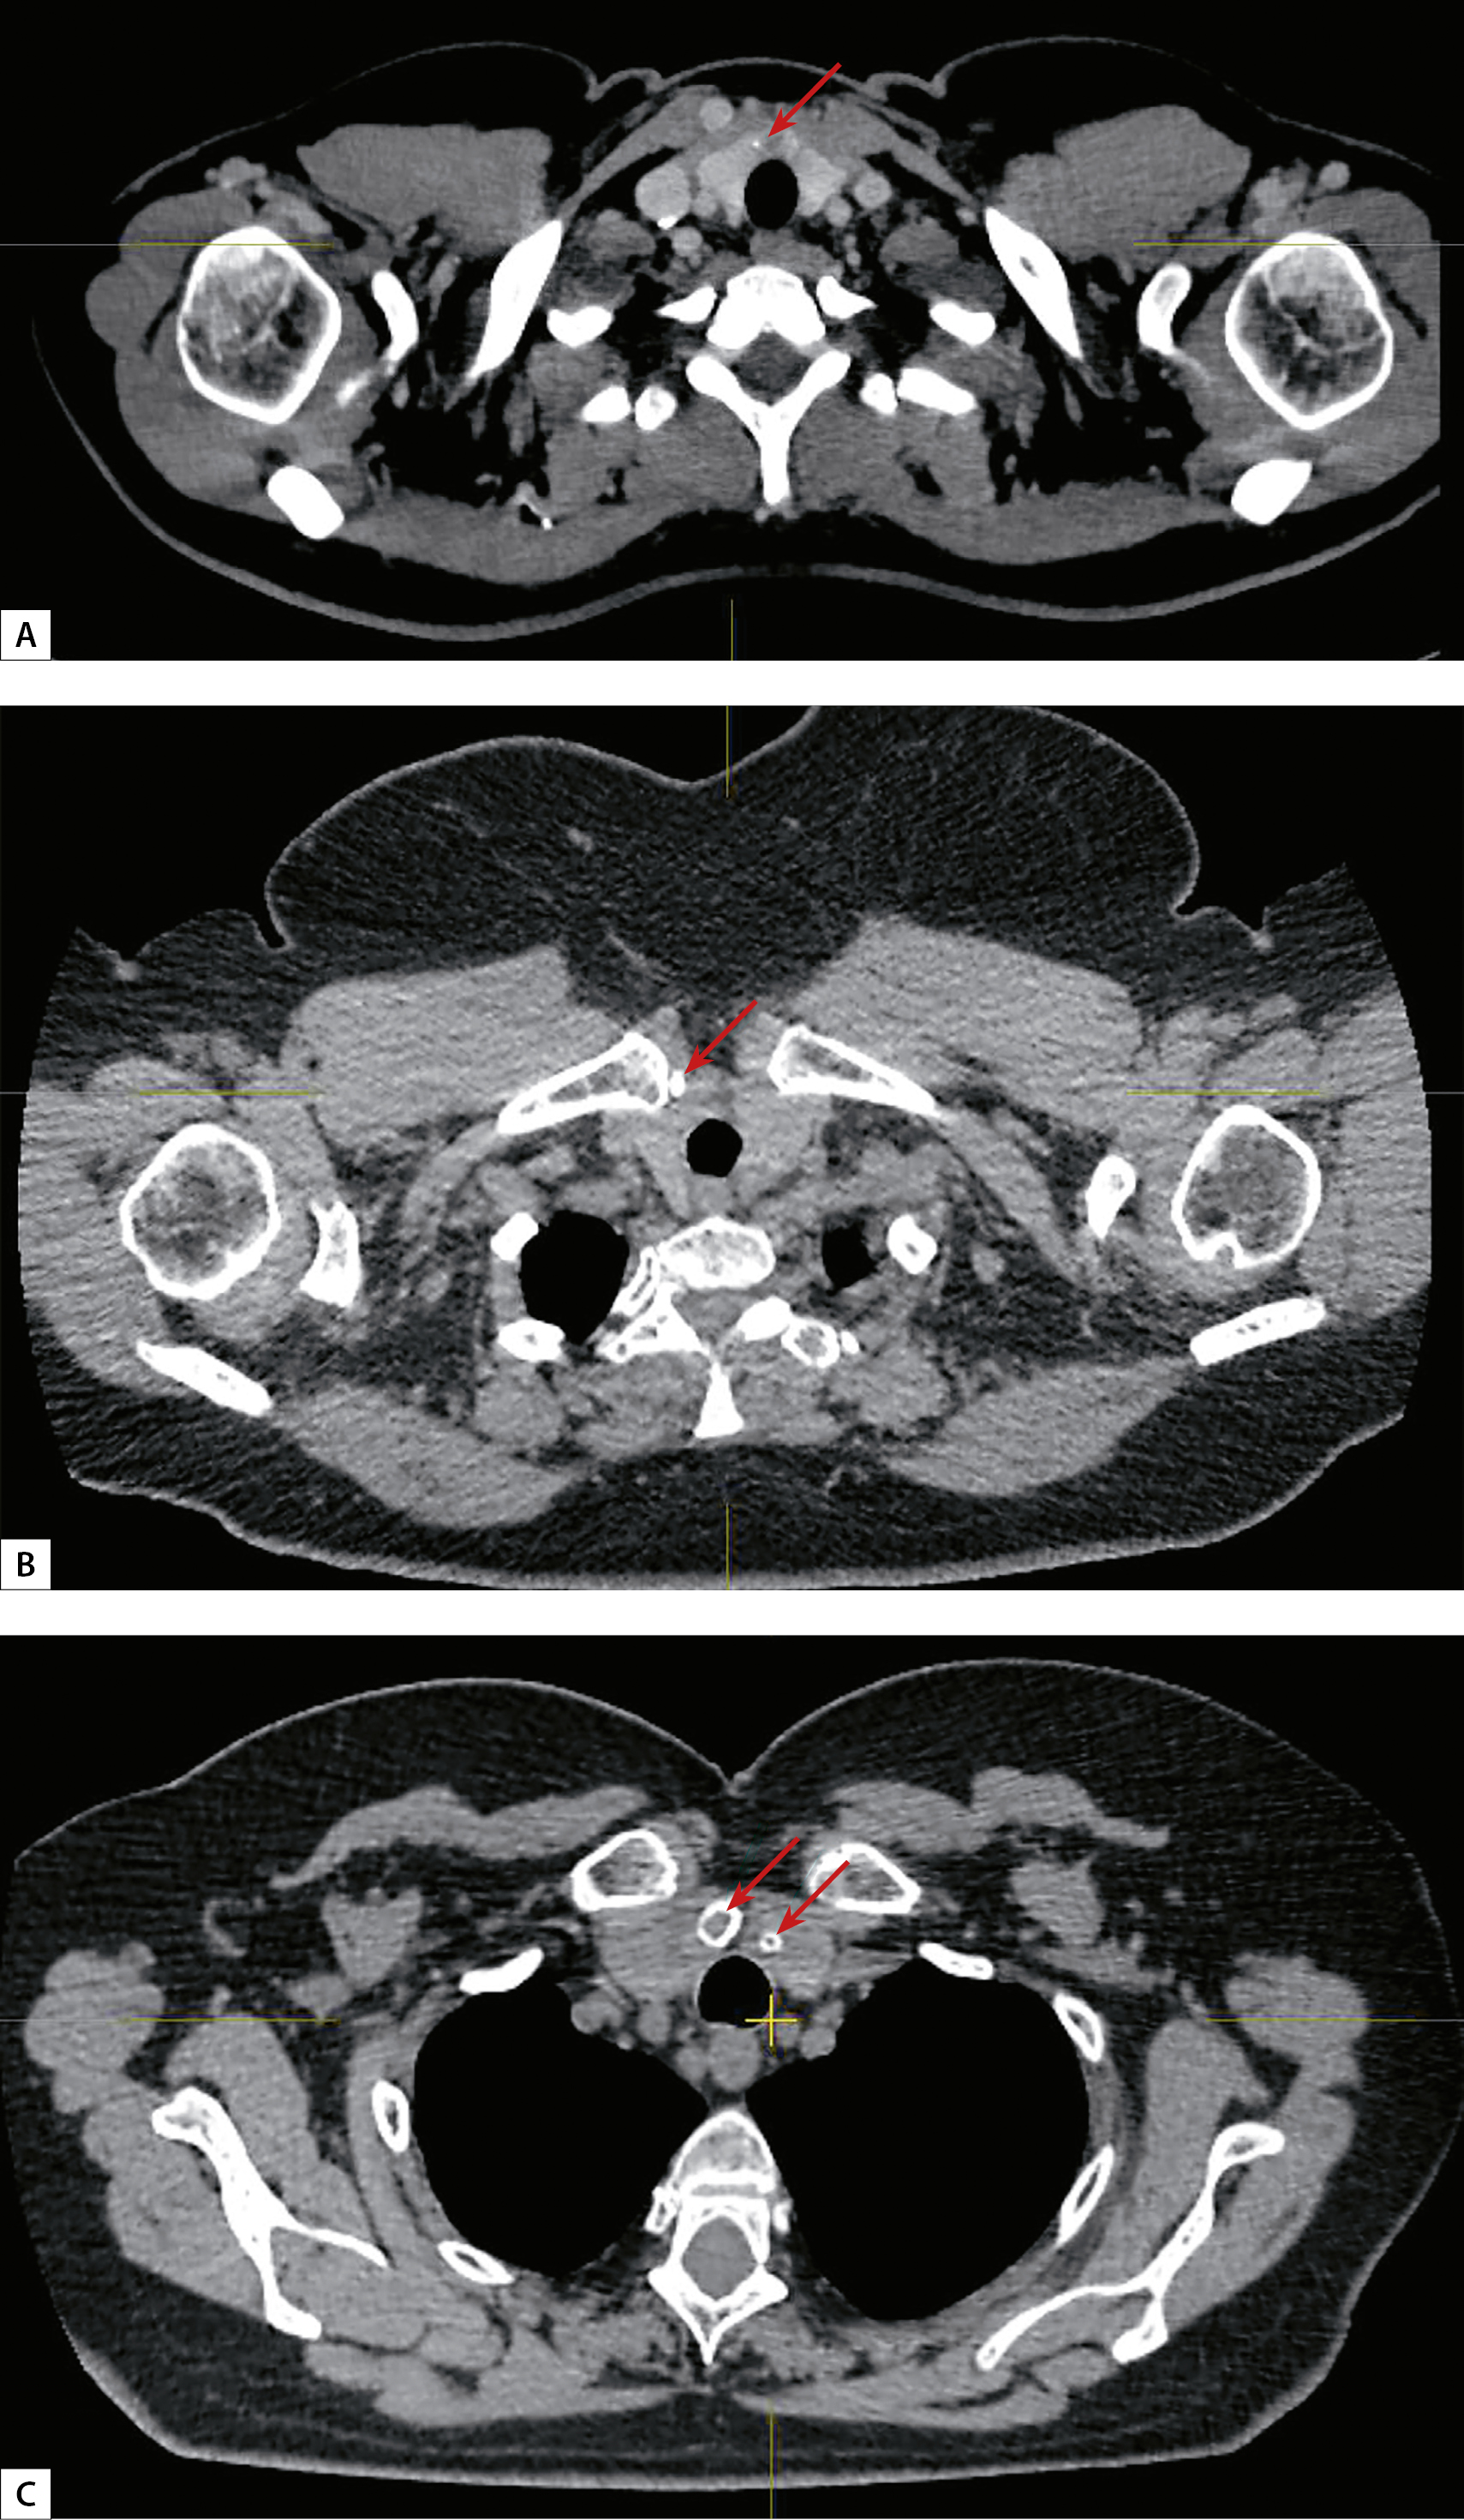

5. Рисунок 5. КТ-картина множественных образований обеих долей щитовидной железы (аксиальный срез, образование указано стрелкой). | |